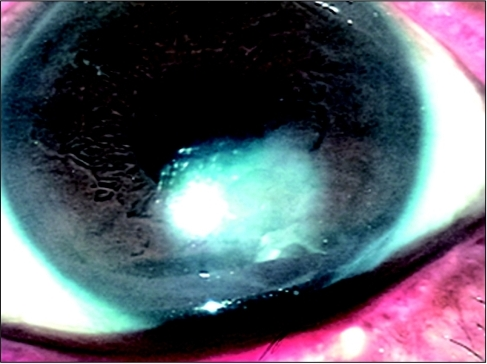

| 2 | 상피결손(PED), 주변부에 부종 |

| 3 | 궤양, 실질 용해, 천공 위험 |

NK의 핵심: (1) 각막감각 소실, (2) 무통성 궤양 (환자가 모를 수 있음), (3) HSV/VZV가 가장 흔한 원인, (4) Cenegermin = 첫 FDA 승인 치료제